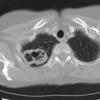

Case 14 RLL pneum CT

Date: 04/17/2005

Views: 5640